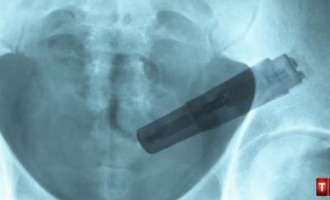

Απίστευτο: Είχε μέσα στον κόλπο της ξεχασμένο δονητή για 10 χρόνια!

Είχε στον κόλπο της ερωτικό παιχνίδι για 10 χρόνια χωρίς να το έχει αντιληφθεί! Μία 38 χρονη γυναίκα από την Σκωτία…